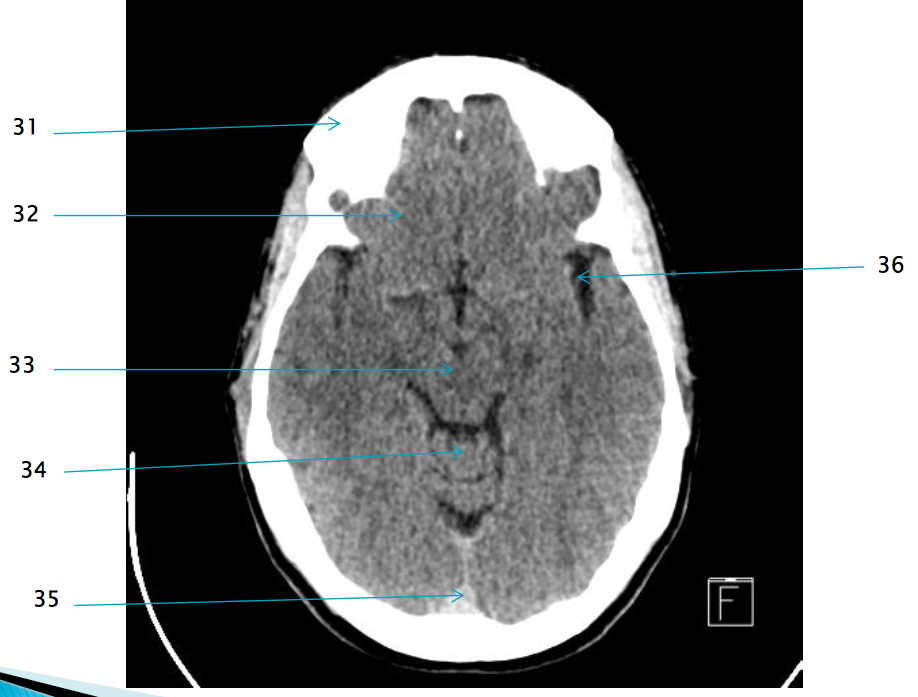

35

Superior sagittal sinus

32

R frontal lobe

37

Frontal horn of R lateral ventricle

22

R temporal bone

29

Pre pontine cistern

28

L anterior clinoid process

38

Septum pellucidum